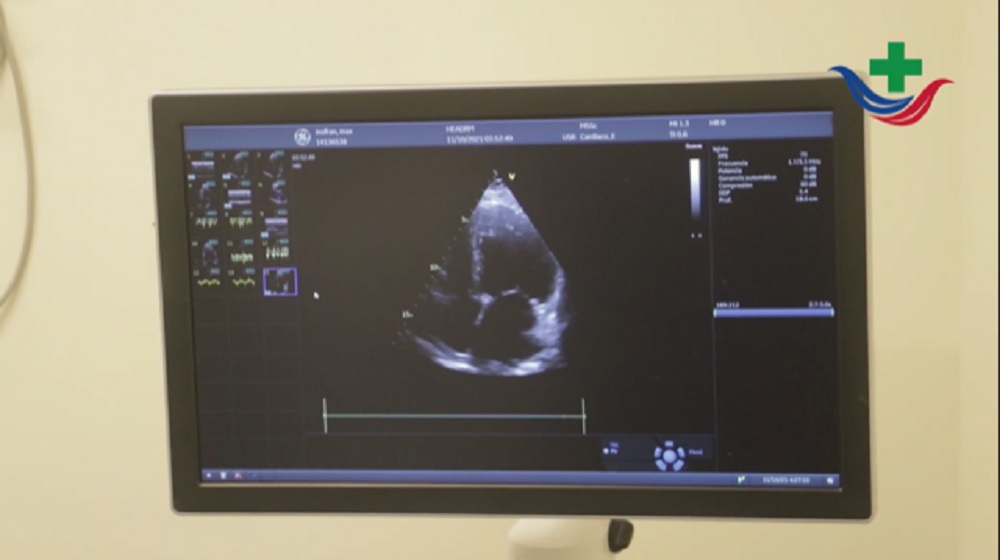

“En el Hospital Escuela se realizan eco doppler cardíacos, de vasos de cuello, ecotransesofágicos, ecoburbujas, ecoestrés, todo lo que tiene que ver con la ecografía cardíaca, arterial y venosa”; a lo que agregó en cuanto a la relación del personal con que cuentan que “son 10 ecocardiografistas en el sector, que se especializan en algún tipo de ecografía”.

En relación a la especialidad, la profesional explicó que es una prestación multidisciplinaria “se atienden a pacientes que están internados en clínica médica, en cirugía, en terapia, unidad coronaria, son pacientes que requieren algún tipo de estudio cardiológico o vascular cuando tienen catéter venosos, abarcamos todos los servicios que requieran estudios”.